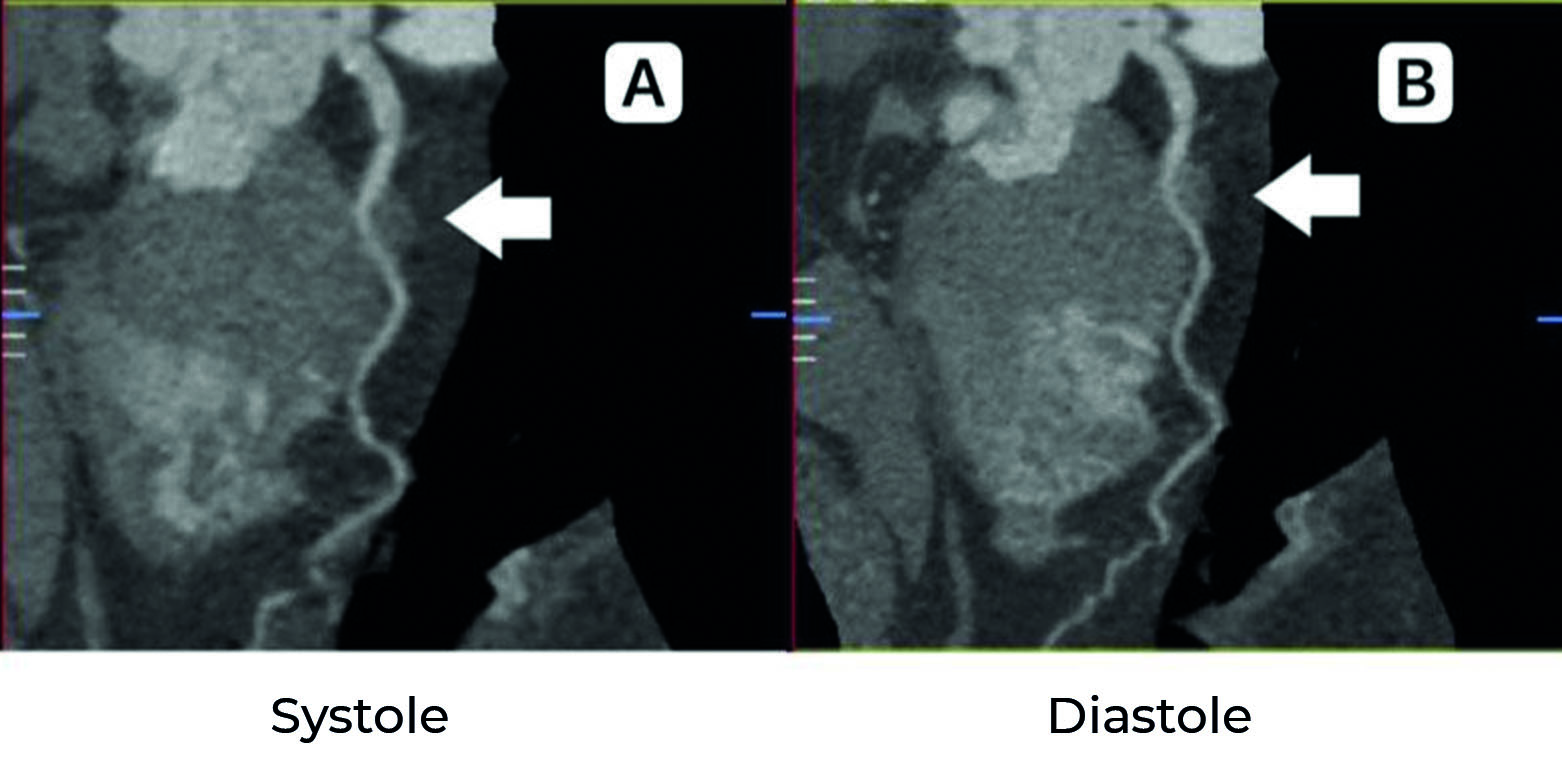

В дополнение к вышеописанным механизмам патофизиологические изменения в миокарде в течение жизни могут вызывать симптомы ИМ у пациентов, ранее не испытывавших никаких симптомов. Во-первых, увеличение диастолической дисфункции левого желудочка, связанное со старением, гипертонией и коронарным атеросклерозом, может усугубить вызванное мостиком несоответствие между спросом и предложением кровоснабжения. Во-вторых, развитие гипертрофии левого желудочка может усилить компрессию и снизить коронарный микрососудистый резерв (рисунок 5).

Рисунок 5. A: Сердце с ММ, молодой возраст, ранняя стадия. 1 – продольный разрез ММ. В: Сердце с ММ, пожилой возраст, поздняя стадия, с гипертрофией желудочков и диастолической дисфункцией. 2 – продольный разрез ММ с гипертрофированной мышцей и прогрессирующей проксимальной атеросклеротической бляшкой (стрелка), негативное ремоделирование сосуда с уменьшением диаметра просвета.

Figure 5. A: Heart with MB, young age, early stage. 1: Longitudinal incision MB. B: Heart with MB, advanced age, advanced stage, with ventricular hypertrophy and diastolic dysfunction. 2: Longitudinal incision of MB with hypertrophied muscle and progressive proximal atherosclerotic plaque (arrow), negative remodeling of the vessel with a decrease in the diameter of the lumen.